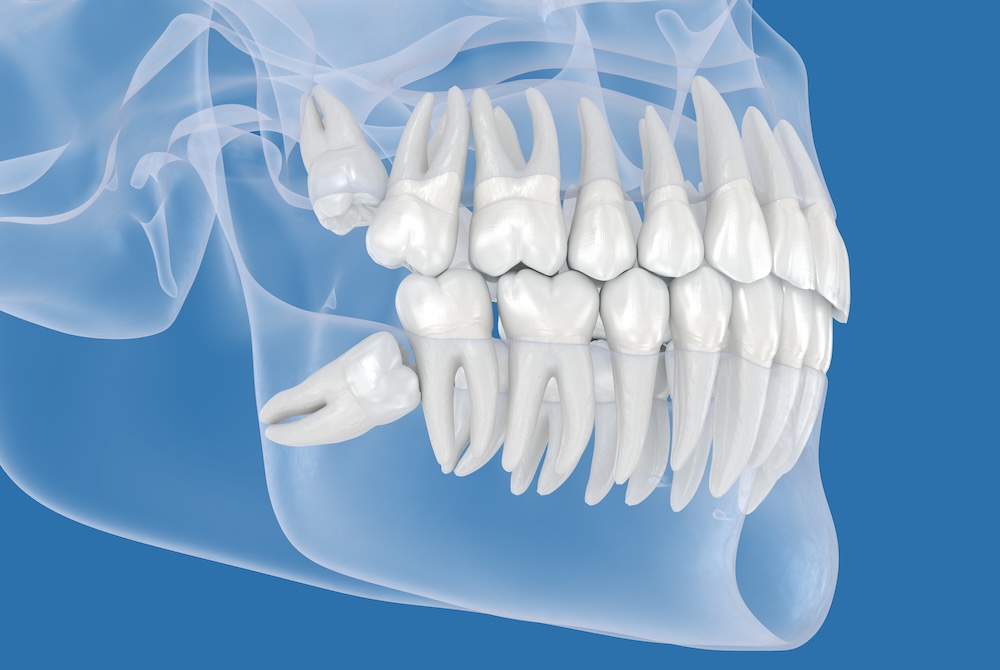

Wisdom teeth are the last set of adult teeth to grow in. Also called "third molars," wisdom teeth are the last set of molars located at the very back of your mouth just behind your second molars. They typically emerge between the ages of 17 and 25, earning them the name "wisdom" teeth because they appear later in life when you're considered "wiser."

Most adults have four wisdom teeth—one in each quadrant of the mouth: Upper left, Upper Right, Lower Left, and Lower Right. Some people have fewer or even none, but four is the most typical number.

Impaction: When there's insufficient space in the jaw, wisdom teeth may become trapped beneath the gum line, leading to pain and potential infection.

Crowding: Wisdom teeth can push against neighboring teeth, potentially causing misalignment or undoing previous orthodontic work.